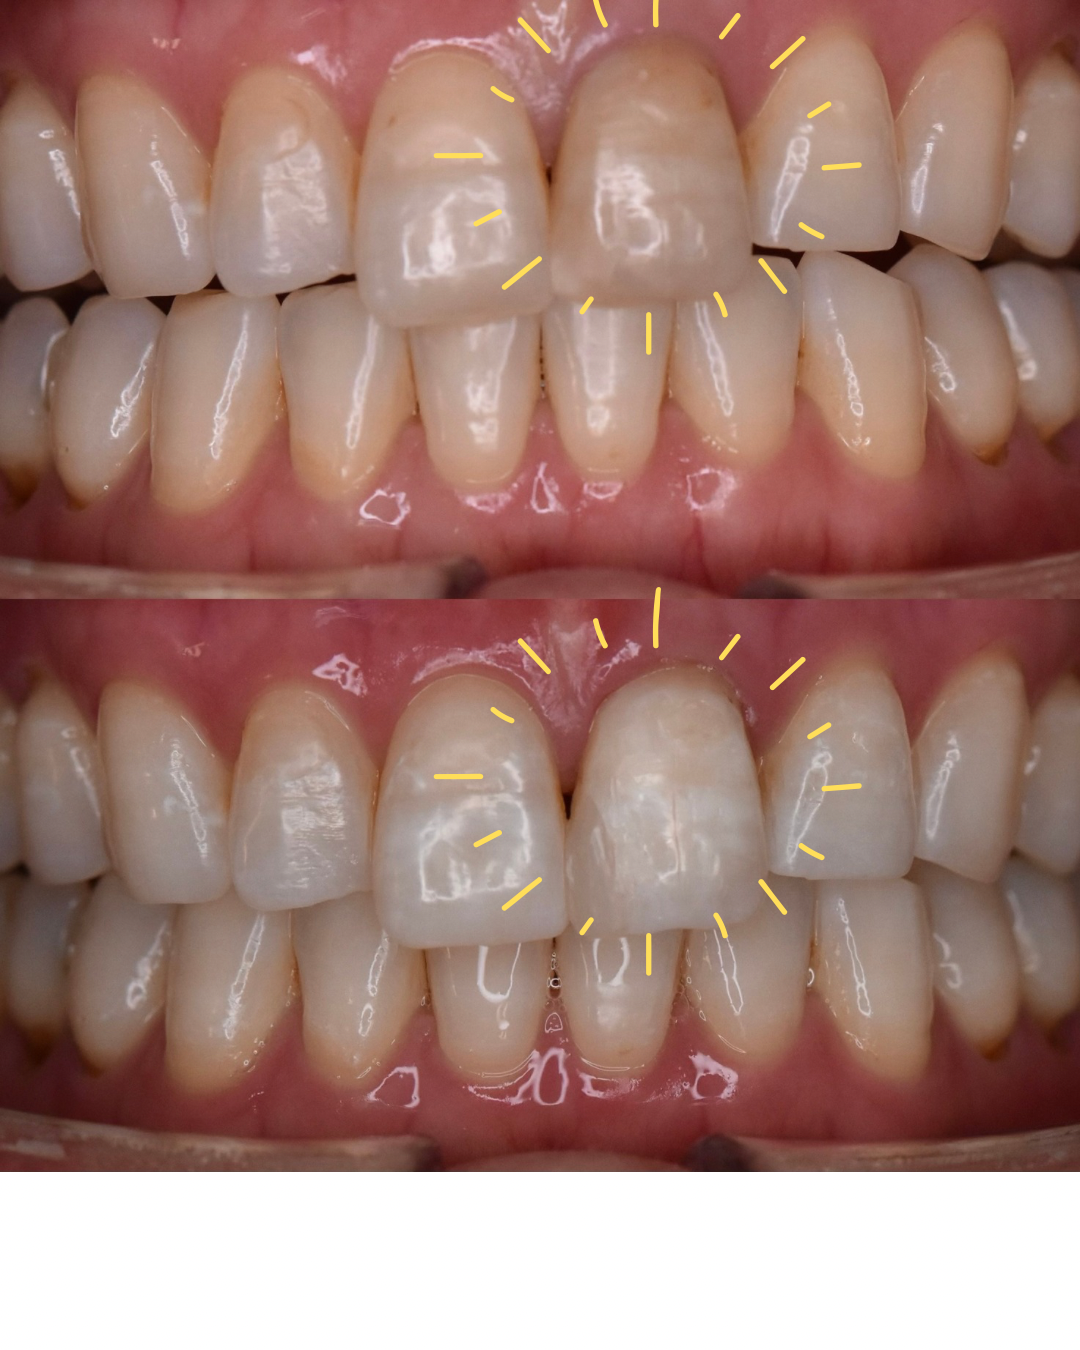

「幼い頃に転んでしまい、前歯の神経がなくなってしまったんです。」

前歯の神経がなくなってから長い年月が経ち、歯の色の変化がずっと気になっていたそうです。

診査を行ったうえで、今回は神経のない歯の治療を行い、前歯の色味を改善。

さらに、歯全体の色を整えるためホワイトニングも同時に行いました。

治療後、鏡を見た患者さまはとても驚かれていました。

「長年悩んでいた歯が、こんなにきれいになるなんて…。

しかも即日で治るなんて信じられません。」

前歯の色が整ったことで、

自信を持てる口元になったと喜んでくださいました。

| 治療期間 | 1日 |

| 治療費用 | 1歯 14,800円 |

| 主訴 | 神経の無い歯を治療してほしい |

| 治療内容 | ウオーキングブリーチ |